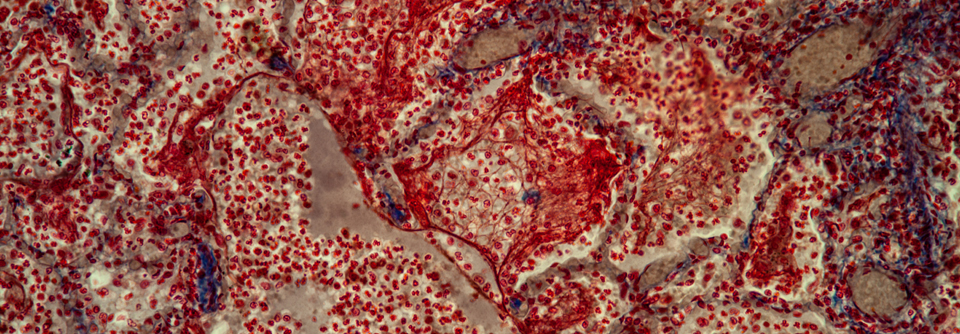

Da bei extrapulmonaler Tuberkulose das Negativwerden des Sputums als Monitoringfaktor ungeeignet ist, müssen Klinik und ggf. die Bildgebung zur Beurteilung des Therapieeffektes herangezogen werden. Da bei extrapulmonaler Tuberkulose das Negativwerden des Sputums als Monitoringfaktor ungeeignet ist, müssen Klinik und ggf. die Bildgebung zur Beurteilung des Therapieeffektes herangezogen werden. © wikimedia/Yale Rosen